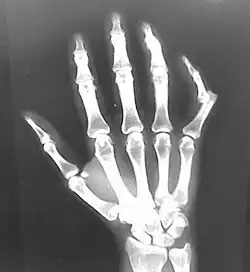

Raios X de uma luxação de dedo

Raios X geralmente são realizados para confirmar o diagnóstico e detectar qualquer fratura que possa ter ocorrido no momento da luxação. Uma luxação é facilmente vista em um raio-X.